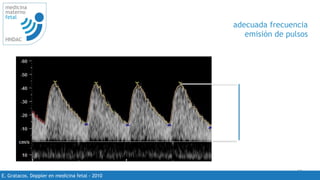

adecuada frecuencia

emisión de pulsos

50 -70%

visualizacion de ondas 4 - 6 ondas

PRF de acuerdo al vaso que se estudia